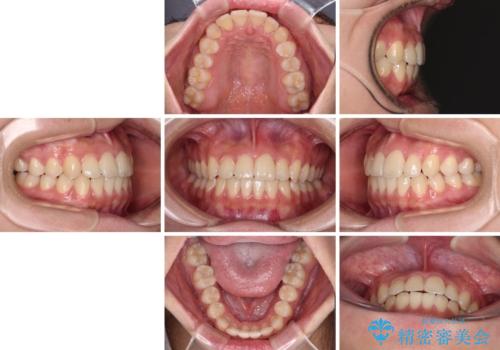

前歯のクロスバイトを短期間で解消 目立たないワイヤー矯正

- 1年1ヶ月

- 前歯のクロスバイトを治したいとのことで来院された患者様です。

できる限り楽して、短期間で治したいとのことで、ワイヤー装置にて矯正治療を行うこととしました。